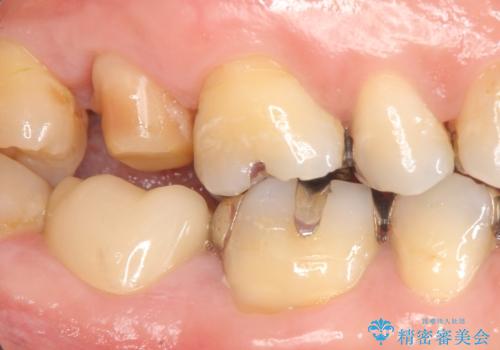

精査したところ、右上の奥歯(右上7)はう蝕が深く骨吸収も進行しており保存不可能な状態でした。

金属アレルギーの疑いがあり、インプラントも避けたいとの患者様のご希望により、親知らずを移植することにしました。

移植がうまくいかない可能性を考慮し、ブリッジもできるよう隣の親知らず(右上8)は残し、反対側の親知らず(左上8)を移植しました。